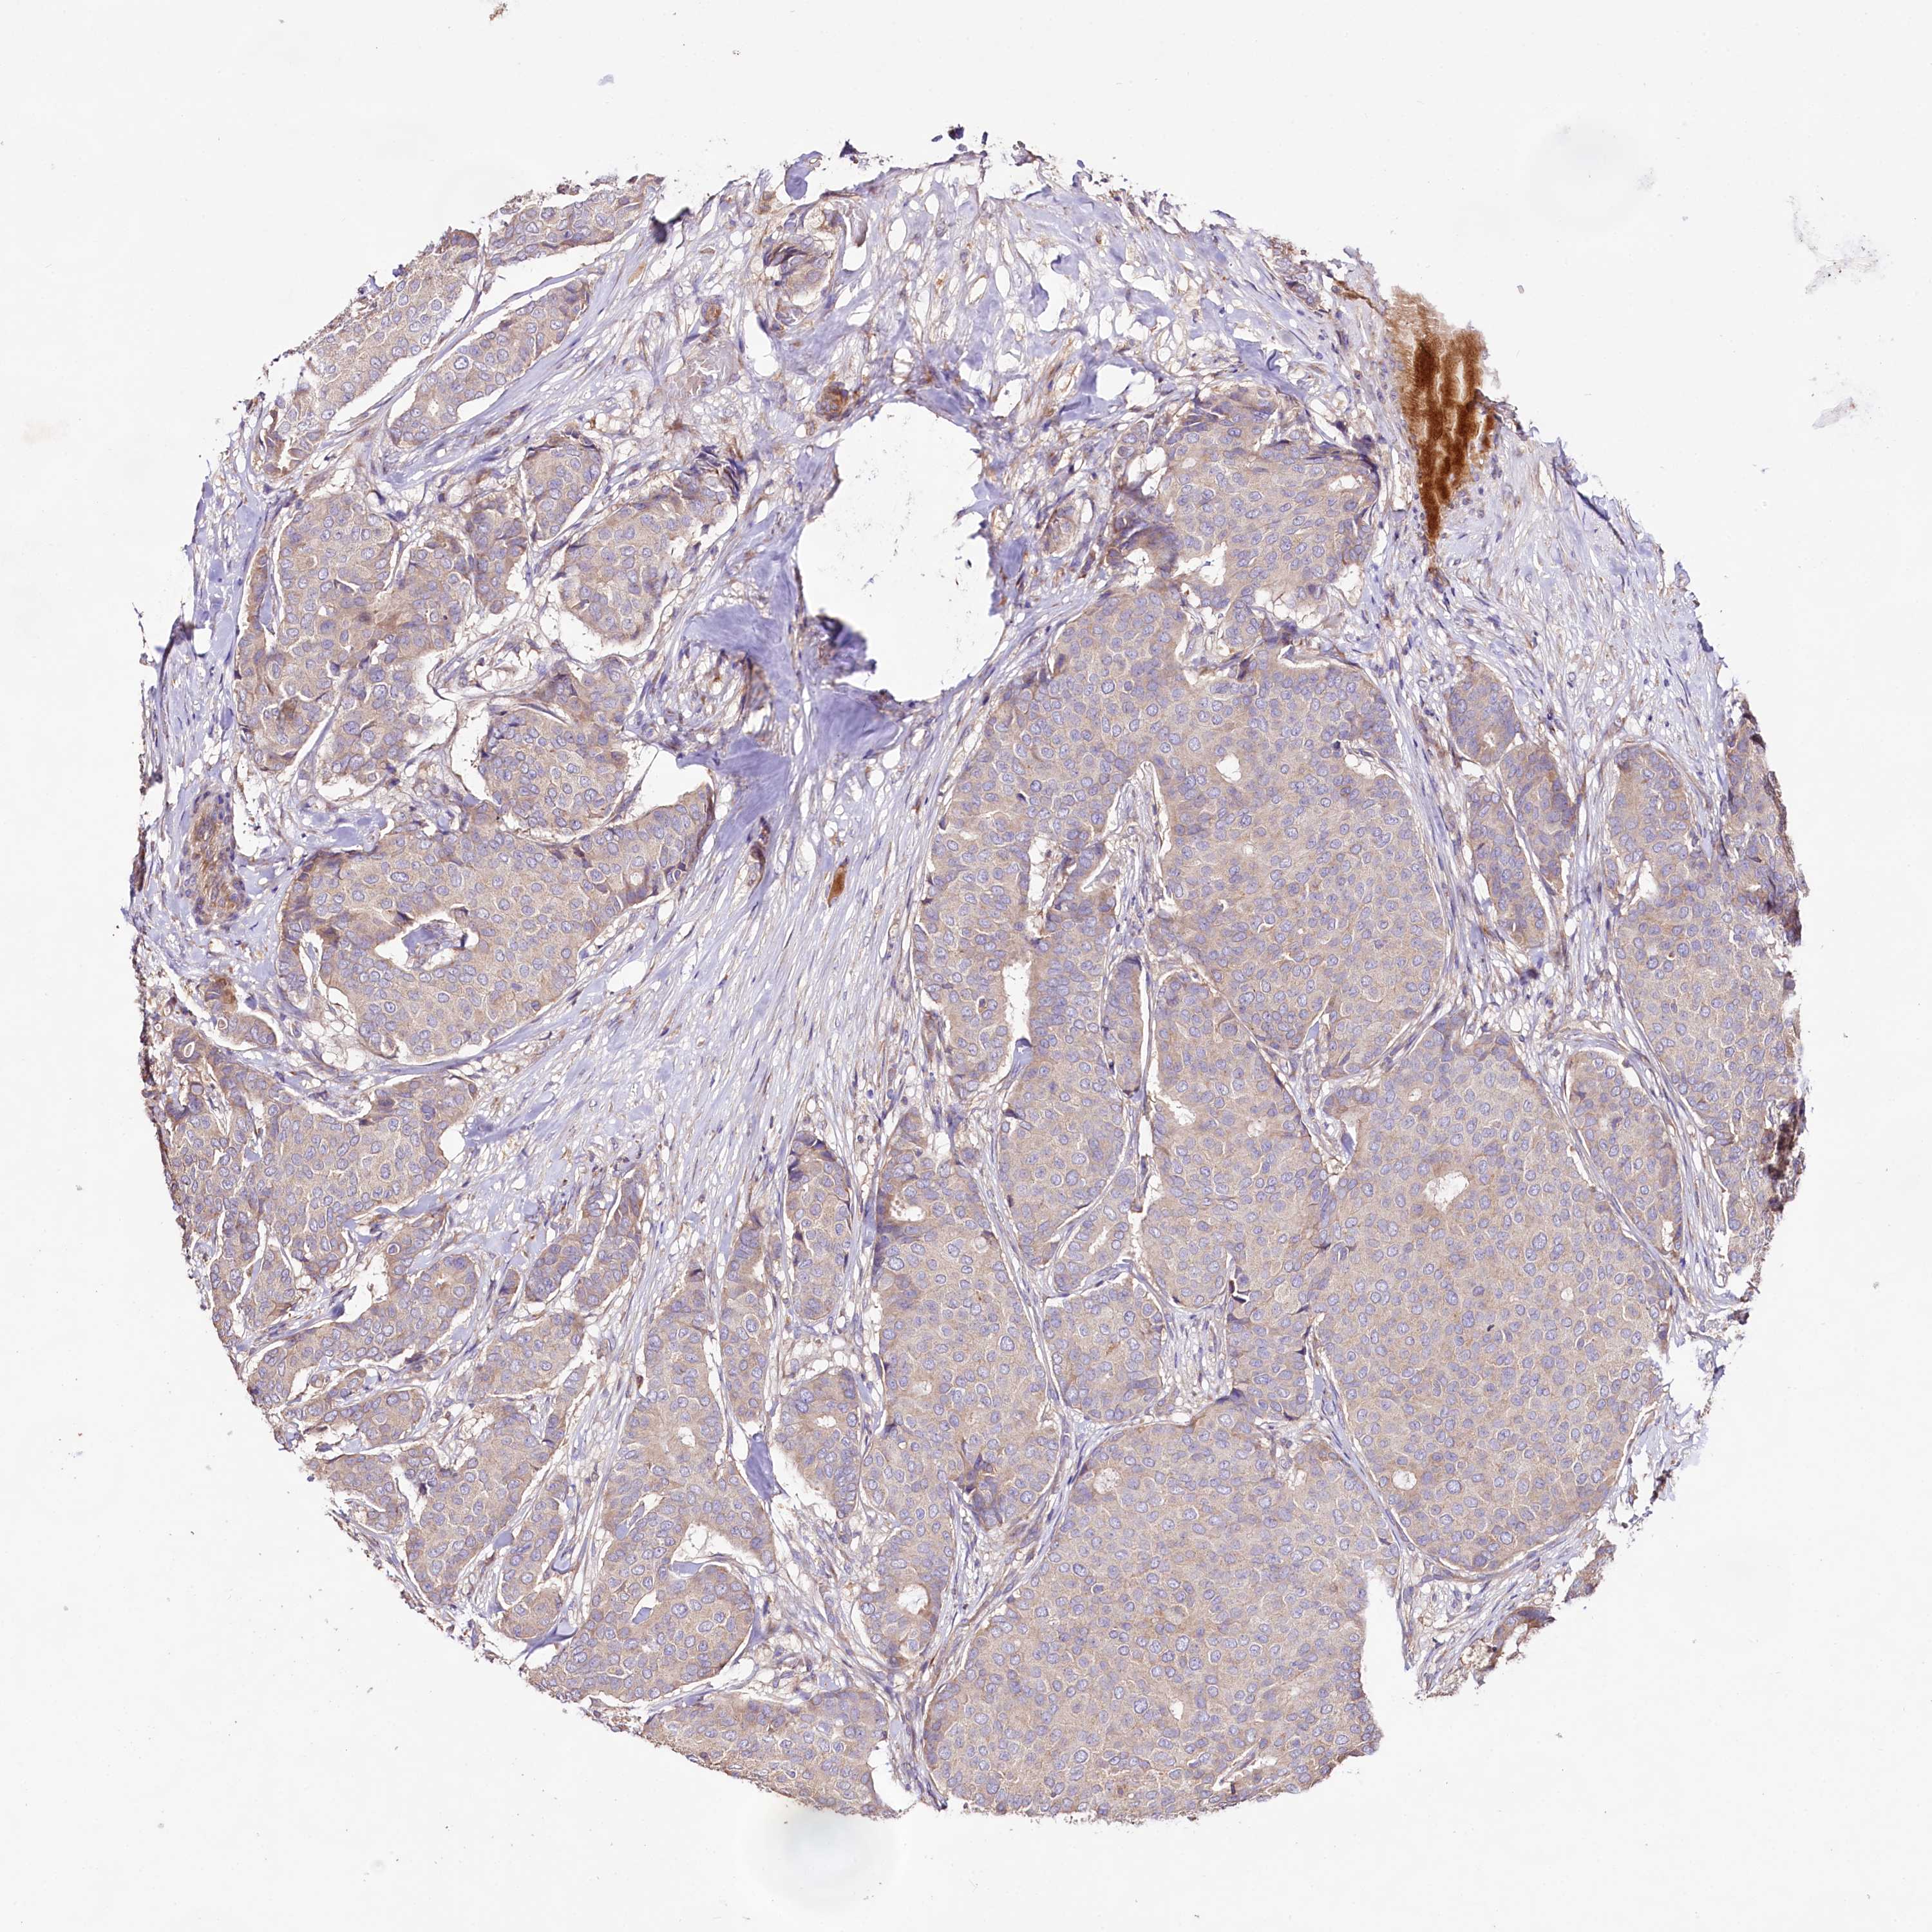

BRCA TCGA BRCA VALIDATION PROTEIN EXPRESSION

ANTIBODIES

AND

VALIDATION